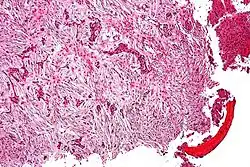

| Micrograph (using H&E stain) of an adamantinoma showing the biphasic histomorphology. | |

Histologically, islands of epithelial cells are found in a fibrous stroma. The tumor is typically well-demarcated, osteolytic and eccentric, with cystic zones resembling soap bubbles.[2]